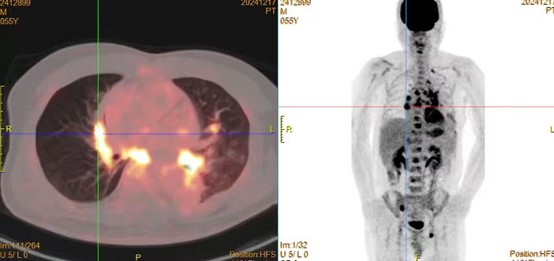

靶向治疗虽然效果显著,但耐药问题常见。本例患者在治疗7个月后出现耐药,肿瘤发生肝和骨髓转移。给予患者肝穿刺再活检明确耐药机制。后患者出现不明原因出血,实验室检查血小板、血红蛋白和纤维蛋白原进行性下降。唐晓勇主任及时与患者就诊的山东第一医科大学第二附属医院刘海燕主任团队沟通,最后考虑为肿瘤进展引起的DIC纤溶亢进。患者生命垂危!就在这千钧一发的时刻,基因检测结果回示ALK和RET双融合突变,立即给予针对洛拉替尼和塞普替尼双靶药物联合治疗,2天后患者症状明显好转,5天后血检结果恢复正常患者出院。